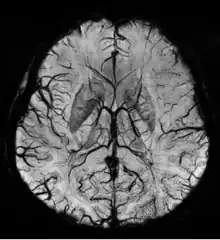

Susceptibility weighted imaging (SWI), originally called BOLD venographic imaging, is an MRI sequence that is exquisitely sensitive to venous blood, hemorrhage and iron storage. SWI uses a fully flow compensated, long echo, gradient recalled echo (GRE) pulse sequence to acquire images. This method exploits the susceptibility differences between tissues and uses the phase image to detect these differences. The magnitude and phase data are combined to produce an enhanced contrast magnitude image. The imaging of venous blood with SWI is a blood-oxygen-level dependent (BOLD) technique which is why it was (and is sometimes still) referred to as BOLD venography. Due to its sensitivity to venous blood SWI is commonly used in traumatic brain injuries (TBI) and for high resolution brain venographies but has many other clinical applications. SWI is offered as a clinical package by Philips and Siemens but can be run on any manufacturer's machine at field strengths of 1.0 T, 1.5 T, 3.0 T and higher.

SWI uses a fully velocity compensated, RF spoiled, high-resolution, 3D gradient recalled echo (GRE) scan. Both the magnitude and phase images are saved, and the phase image is high pass (HP) filtered to remove unwanted artifacts. The magnitude image is then combined with the phase image to create an enhanced contrast magnitude image referred to as the susceptibility weighted (SW) image. It is also common to create minimum intensity projections (mIP) over 8 to 10 mm to better visualize vein connectivity. In this way four sets of images are generated, the original magnitude, HP filtered phase, susceptibility weighted, and mIPs over the susceptibility weighted images.